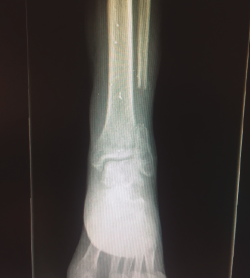

La fractura del peroné se trató de forma conservadora (Figura 4).

Figura 4. Radiografía tomada 5 meses después, tras el tratamiento conservador.